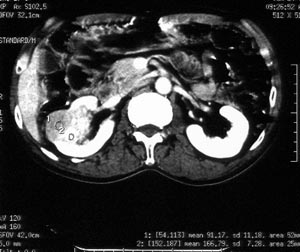

男性,56岁。右腰部不适2月。无血尿,无尿频尿急尿痛。b超提示:右肾下极占位。

ct平扫加增强扫描:右肾中下极肾盂外侧段实质见分叶状软组织密度肿块,截面大约56x45mm,向外突破肾包膜,向内突入肾盂,平扫密度略不均,ct值32-37hu。c+见病灶不均匀轻-中度强化,内有未强化坏死区。右侧肾周筋膜增厚,右肾内前方见肿大淋巴结。

ct诊断:右肾癌,ct表现见上述,伴同侧腹膜后淋巴结转移。

手术所见:右肾大小15x7cm,背侧有肿物突出肾包膜,大小7x4cm。行“右肾癌根治术”。

手术病理:

透明细胞癌(ⅰ-ⅱ级)